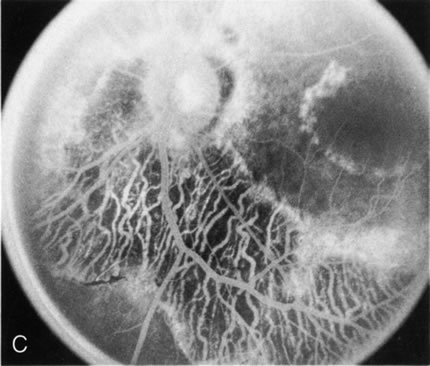

Of more clinical importance is the role of FA in the diagnosis and treatment of cystoid macular edema (CME) (Fig. 1C and D). Stereoscopic FA indicates that the leakage, which may be diffuse or have the typical petaloid stellate appearance of CME, can come from the perifoveal retinal capillaries, from the choroid through the RPE, or from a combination of both sources.4 With the recent suggestion that CME in RP may be successfully treated with acetazolamide,5, 6 FA is thus important to document the diagnosis of CME, establish the origin(s) of leakage, and follow patients during and after therapy.